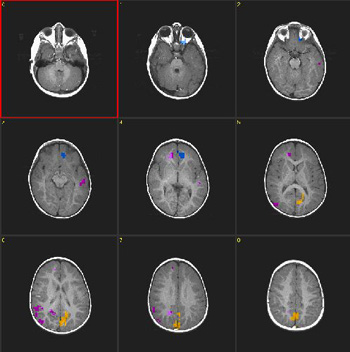

| Caso 4 |

| Paciente |

Niño normal de 18 meses de edad

Paradigma

n.° 2: |

ACTIVADO: Presentación de luces intermitentes a 8 Hz

DESACTIVADO: Nada. Paciente sedado con hidrato de cloral |

| Estadísticas |

| Método estadístico |

Valor P |

Puntuación Z |

| Prueba T |

0,0005 |

3,3 |

| Imagen |

ACTIVADO-DESACTIVADO

DESACTIVADO-ACTIVADO

| Activación |

Hay activación bilateral de la corteza motora y "desactivación" de la región anterolateral de la fisura calcarina (periférico V1) como se observa en el caso n.° 3. La ubicación de esta respuesta es previsible, debido a que el tipo de estímulo usado aquí causa mayor activación de la retina periférica que de la fóvea. La activación de las áreas motoras a través de estímulos visuales es similar a la obtenida con la voz de la madre en el caso n.° 1. |